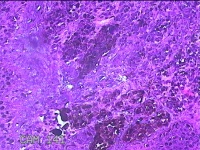

后颈部结节

性别

女

年龄

25岁

临床诊断

皮下结节

一般病史

发现后颈部“黑痣”20余年,伴近日局部瘙痒不适。

标本名称

大体所见

灰白粉红色带皮肤结节0.8x0.7x0.3cm一个,表面糜烂,切开结节呈实性,切面灰白粉红色,质软。

皮内痣